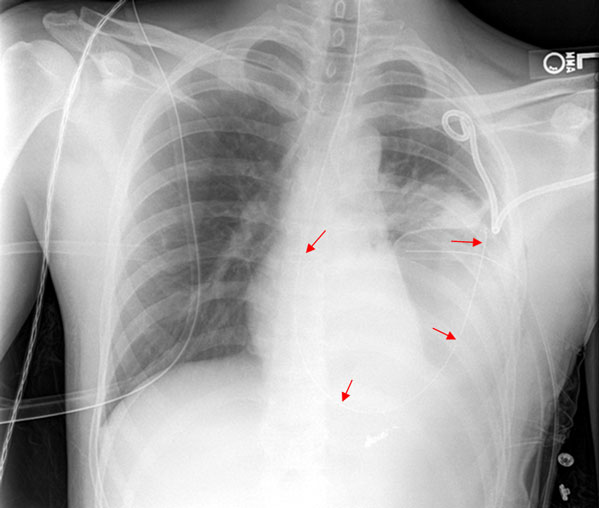

Pneumothorax

A patient with a tension pneumothorax will have the following clinical features:

Trauma to the chest (e.g. GSW, stabbing)

Distended head and neck veins (high CVP)

Hypotension

Severe respiratory distress

On physical exam of the chest of a patient with tension pneumothorax, the affected side has no breath sounds and is hyperresonant to percussion. On x-ray, the mediastinum is displaced to the opposite side,marked most notably by tracheal deviation.

Since a tension pneumothorax is a clinical diagnosis and a medical emergency, NO chest x-ray or other study is necessary and is contraindicated. Management is insertion of a large-bore needle or IV catheter into the pleural space (inserted high on anterior chest wall in the second intercostal space) then insertion of a chest tube and connect it to underwater seal and suction (chest tube also inserted high on anterior chest wall).

The first three steps in management of a tension pneumothorax are:

Emergent needle decompression, inserted into the 2nd intercostal space

Chest tube (tube thoracostomy), inserted into the 5th intercostal space

Intubation, if still necessary

Note that diagnostic imaging plays no role in the emergent stabilization of these patients.